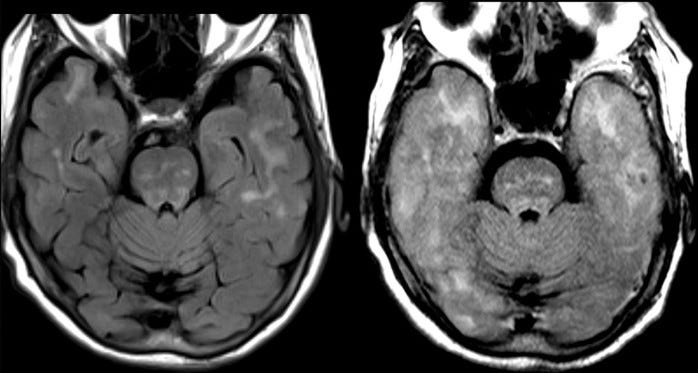

A tiny slowing of the decline by 0.45 points. The catch here is side effects. We’ve learnt how to read a paper,⌘ reconciling the Abstract with the rest. Here, the abstract mentions “amyloid-related imaging abnormalities with edema or effusions in 12.6%”. Death is not mentioned.

The Results section describes “discontinuation of [lecanemab] in 6.9%” against 2.9% in the placebo group, brain swelling in 12.6% versus 1.7%, and brain bleeds in 17.3% versus 9%.5 They assure us that there were no drug-related deaths. Here, they may have been economical with the truth, as there is now evidence of three such deaths. The MRI images at the start of this section are before-and-after pictures of one woman who died in the study. The pale fuzziness in her brain on the right hand image represents brain swelling. Donanemab seems similar.